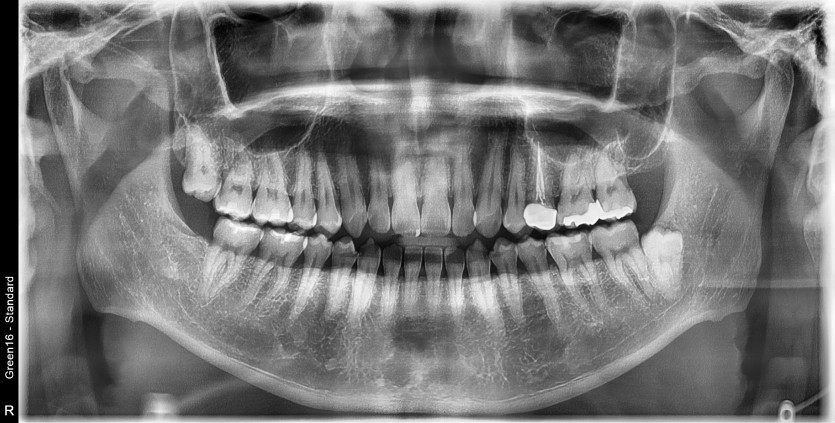

#18 사랑니 발치

구강 외과 전문의가 당일 발치했습니다.